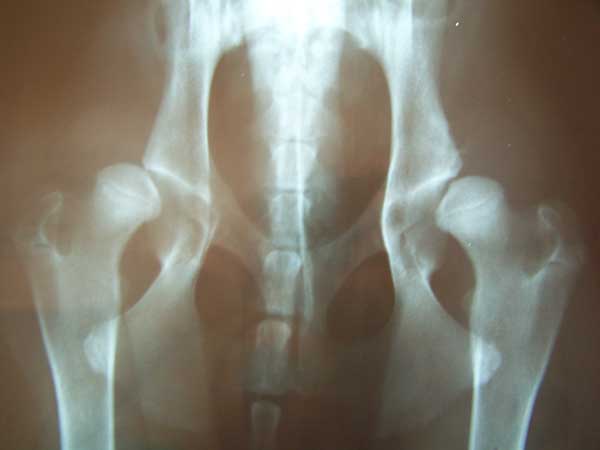

R: Moltissime, anche perché sto eseguendo diversi interventi di sinfisiodesi pubica giovanile, una tecnica chirurgica che ritengo assolutamente geniale. L’obiettivo è quello di modificare l’inclinazione del bacino ancora in crescita, determinando la chiusura precoce di alcuni punti della sinfisi pubica tramite l’utilizzo di un elettrobisturi, mentre il resto viene lasciato libero di crescere.

Il risultato è quello di avere un acetabolo maggiormente “coprente” e quindi un’articolazione decisamente più stabile: cani con gravi displasie, operati precocemente, a un anno possono risultare “0” alla lettura ufficiale…ed è per questo che spiego sempre ai proprietari che accetterò di operare il cane solo se mi sarà consentito, durante lo stesso intervento, di sterilizzarlo. Un soggetto che da cucciolo manifesta già segni clinici di displasia va assolutamente tolto dalla riproduzione.